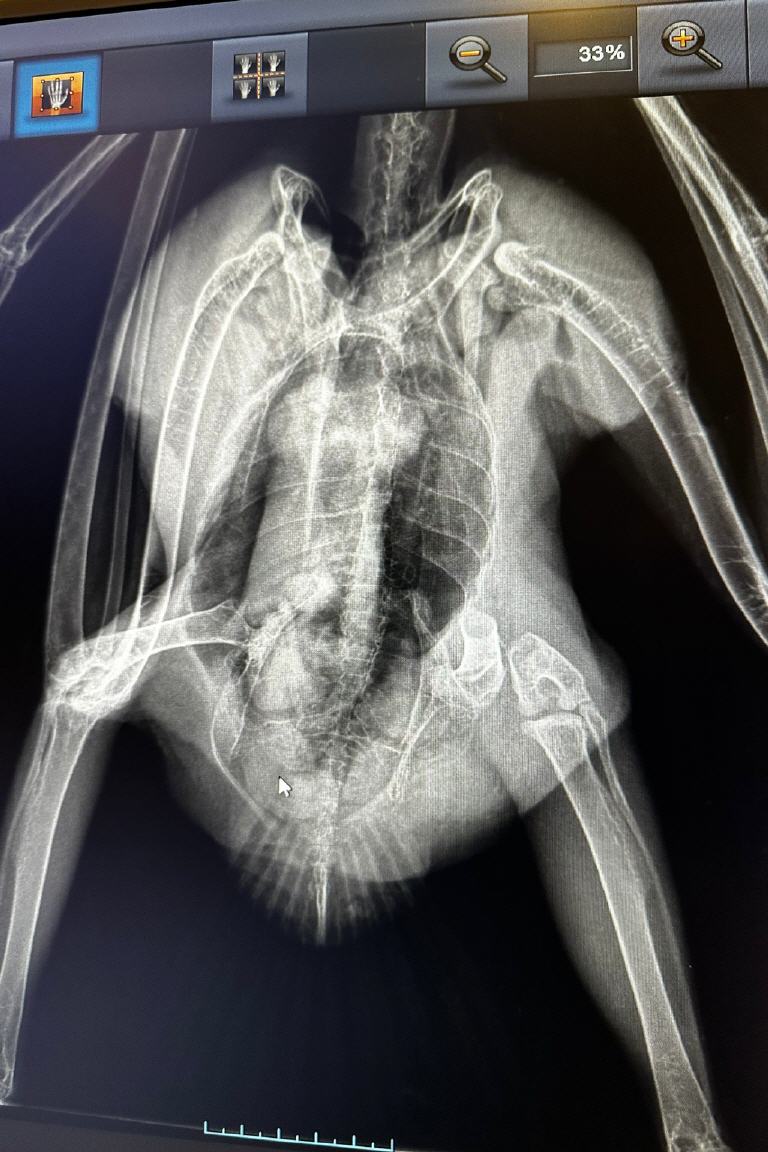

In Fürth sorgt ein ungewöhnlicher Zufall für Aufsehen. Rainer Hussong, Tierarzt und Betreiber der Auffangstation für Greifvögel in Fürth Oberfürberg, hat innerhalb nur einer Woche gleich zwei verletzte Fischadler aufnehmen müssen. Diese Vögel, die in Bayern eher selten anzutreffen sind, haben sich beide verletzt – einer davon schwer – und wurden in Hussongs Station in Obhut genommen. „So etwas habe ich in den letzten dreißig Jahren noch nie erlebt“, sagt Hussong, der seit Jahrzehnten verletzte Greifvögel versorgt und wieder in die Natur entlässt. Über den ersten Fall hatten wir bereits vor einer Woche berichtet. Wir haben die Auffangstation besucht und uns nach den Fischadlern erkundigt (Video).